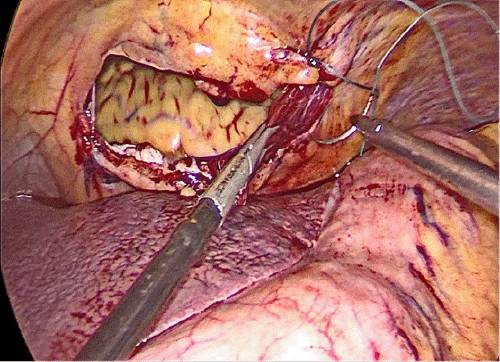

As the patient was hemodynamically stable and there was no internal bleeding, we decided to proceed with laparoscopic surgery with the possibility of conversion at any time if the patient became hypotensive. The patient signed the consent form and underwent surgery after proper preparation. Following induction of anesthesia, bilateral 28-Fr chest tubes (Polymed Medical Devices, Haryana, India) were inserted; 200 mL (0.2 × 10-3 m3) of blood was drained from the left tube, while the right tube did not have any observable output. The patient was stable enough to proceed to laparoscopic surgery. The abdominal cavity was approached from a supraumbilical incision using the open Hasson technique. Two 5-mm trocars (Covidien, Mansfield, MA, USA) were inserted from the left and right subcostal areas under laparoscopic visualization. Upon entering the abdominal cavity, we observed a central diaphragmatic defect communicating with the pericardial space. The heart was seen beating through the 8 cm diaphragmatic defect, with no perceptible damage or free blood in the abdomen (Figure 4). There was a small injury on the edge of the left lobe of the liver without any active bleeding, the stomach was mildly distended with no perceptible injury, there was no splenic injury, and the bowel and mesentery looked normal and healthy. The defect was closed by running a 2-0 tension-free, nonabsorbable suture; three interrupted stitches were placed along the suture line for reinforcement, and a composite mesh of 10 × 15 cm (Symbotex™ composite mesh; Covidien, Walpole, MA, USA) was used to cover the repair and was fixed to the diaphragm with absorbable tacks (AbsorbaTack™; Covidien, Walpole, MA, USA) (Figure 5).

Figure 4. Intraoperative View of Ruptured Central Diaphragm with Clear Window to Pericardial Space. A) Remote and B) Close Views. Published with Permission

A) Remote View